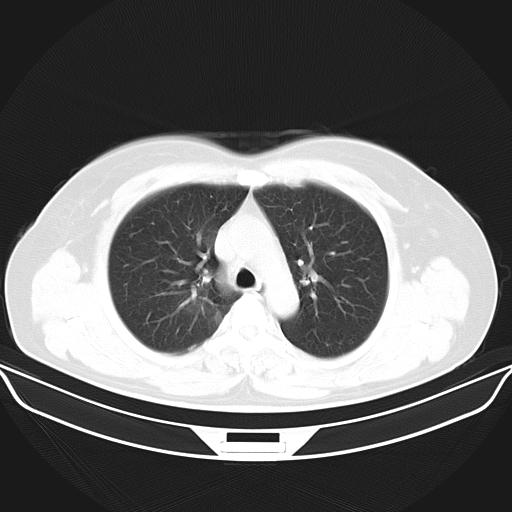

标题: CT22224:肺部肿块

f,48,主因咳嗽咳血来我院检查,无发热。

1)右肺下叶背段团块状软组织密度影;建议抗炎治疗后复查排除肿瘤性病变。2)右侧少量胸腔积液。

谈一谈个人的看法:机器性能应该不错,可惜扫描方法不太正确,即没有及时薄层扫描图像,也没有增强检查,这样的检查方法不正确的图片拿来研究只能是猜一猜:右肺下叶阻塞性改变,建议进一步检查删除肺癌。

支气管镜检查未见异性细胞,抗炎治疗20天,肿块明显缩小。